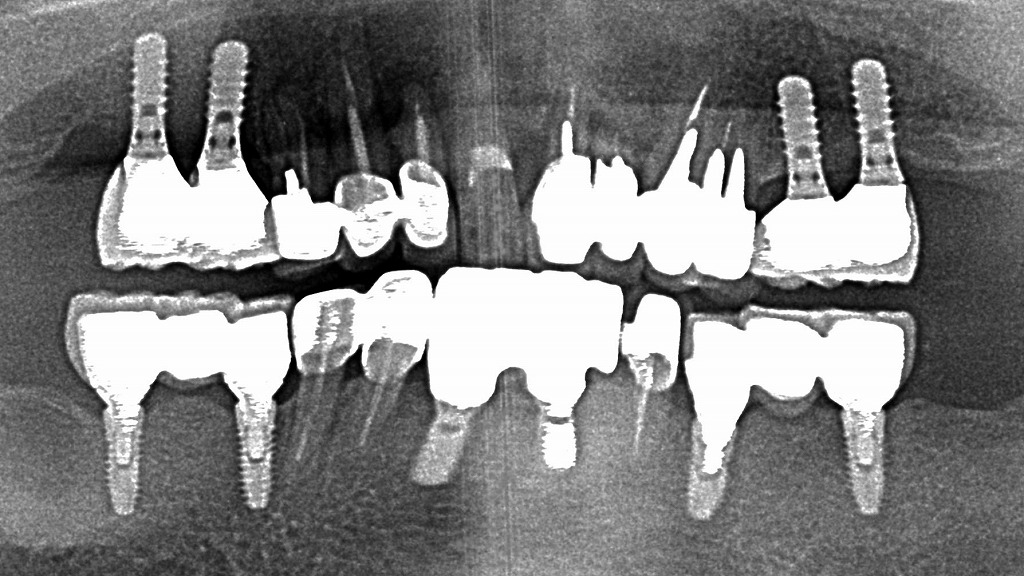

このレントゲン画像は、複数本のインプラントと補綴物が装着されている口腔内の状態を示しています。

エアフローは、微細なパウダーと水流を用いてインプラント表面や上部構造周囲のバイオフィルム(細菌の膜)を効率よく除去できるクリーニング方法です。

金属器具による清掃と比べてインプラント表面を傷つけにくく、インプラント周囲炎の予防・メンテナンスに有効とされています。

定期的なエアフローによるケアは、インプラントを長く安定して使うために重要です。